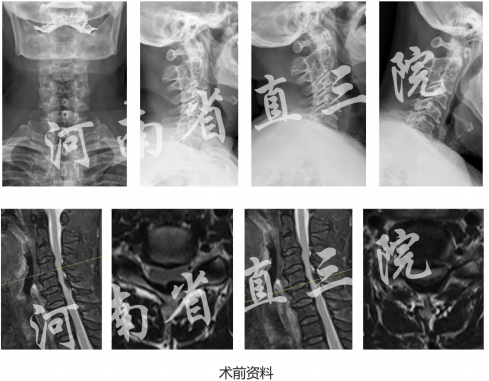

诊断:脊髓型颈椎病(C4/5、C5/6,黄韧带钙化)

手术方案:UBE下C4/5、C5/6全椎板切除椎管减压术